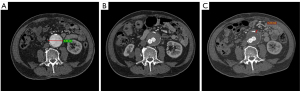

PAF emergence following AAA

An interesting phenomenon was observed in the open surgery group, i.e., the PAF is secondary to AAA progression, as illustrated in Figure 2. A 62-year-old male with known AAA developed PAF during follow-up. He subsequently underwent open repair (OR) for AAA management. The patient’s first CTA scan acquired in December 2017 showed that the abdominal aorta was dilated, with a smooth aortic wall (as shown in Figure 2A). The second CTA scan, obtained in November 2020, showed that PAF emerged (as shown in Figure 2B). Subsequently, progression of both PAF thickness and the maximal diameter of AAA was documented on the third CTA (as shown in Figure 2C) and MRI (as shown in Figure 2D) performed in January 2021. The PAF exhibited mild enhancement in the arterial phase in the MRI (as shown in Figure 2E). Delayed enhancement indicated that the PAF was significantly enhanced (as shown in Figure 2F). These images are all preoperative examinations.